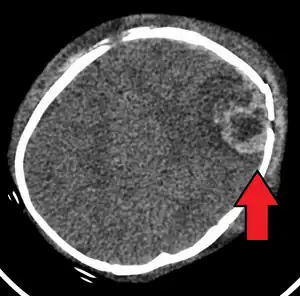

An intraparenchymal bleed with overlying skull fracture from abusive head trauma

Abusive head trauma (AHT), commonly known as shaken baby syndrome (SBS), is an injury to a child's head caused by someone else.[1] Symptoms may range from subtle to obvious.[1] Symptoms may include vomiting or a baby that will not settle.[1] Often there are no visible signs of trauma.[1] Complications include seizures, visual impairment, cerebral palsy, and cognitive impairment.[2][1]

The cause may be blunt trauma or vigorous shaking.[1] Often this occurs as a result of a caregiver becoming frustrated due to the child crying.[3] Diagnosis can be difficult as symptoms may be nonspecific.[1] A CT scan of the head is typically recommended if a concern is present.[1] While retinal bleeding is common, it can also occur in other conditions.[1] Abusive head trauma is a type of child abuse.[4]

Characteristic injuries associated with AHT include retinal bleeds, multiple fractures of the long bones, and subdural hematomas (bleeding in the brain).[5] These signs have evolved through the years as the accepted and recognized signs of child abuse. Medical professionals strongly suspect shaking as the cause of injuries when a young child presents with retinal bleed, fractures, soft tissue injuries or subdural hematoma, that cannot be explained by accidental trauma or other medical conditions.[6]

AHT may be misdiagnosed, underdiagnosed, and overdiagnosed,[26] and caregivers may lie or be unaware of the mechanism of injury.[11] Commonly, there are no externally visible signs of the condition.[11] Examination by an experienced ophthalmologist is often critical in diagnosing shaken baby syndrome, as particular forms of ocular bleeding are quite characteristic.[27] Magnetic resonance imaging may also depict retinal bleeding;[28] this may occasionally be useful if an ophthalmologist examination is delayed or unavailable. Conditions that are often excluded by clinicians include hydrocephalus, sudden infant death syndrome (SIDS), seizure disorders, and infectious or congenital diseases like meningitis and metabolic disorders.[29][30] CT scanning and magnetic resonance imaging are used to diagnose the condition.[11] Conditions that may accompany AHT include bone fractures, injury to the cervical spine (in the neck), retinal bleeding, cerebral bleed or atrophy, hydrocephalus, and papilledema (swelling of the optic disc).[12]